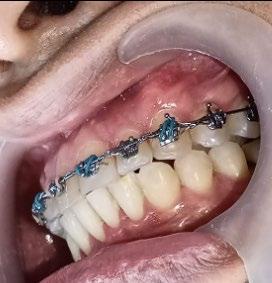

En los estudios intraorales, las fotografías iniciales muestran clase I canina y molar bilateral, mordida anterior abierta, apiñamiento leve superior e inferior, y líneas medias dentales

desviadas. En las Figuras 4, 5 y 6 se observa la forma de las arcadas superior e inferior.

Figura 4. Lateral derecha.

Figura 5. Intraoral de frente e izquierda.